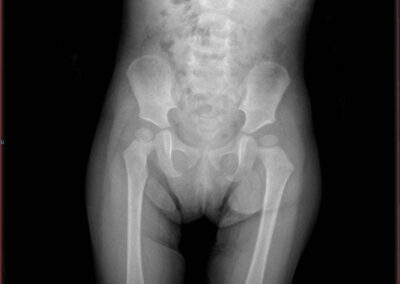

Congenital Pediatric Orthopedic DiseasesDec 30, 2021 | Case ExamplesBilateral GKD Case 1 Bilateral GKD Case 2 Bilateral GKD Case 3 Bilateral GKD Case 4 Congenital Clubfoot Fibuler Hemimeli Tibial Hemimeli PFFD